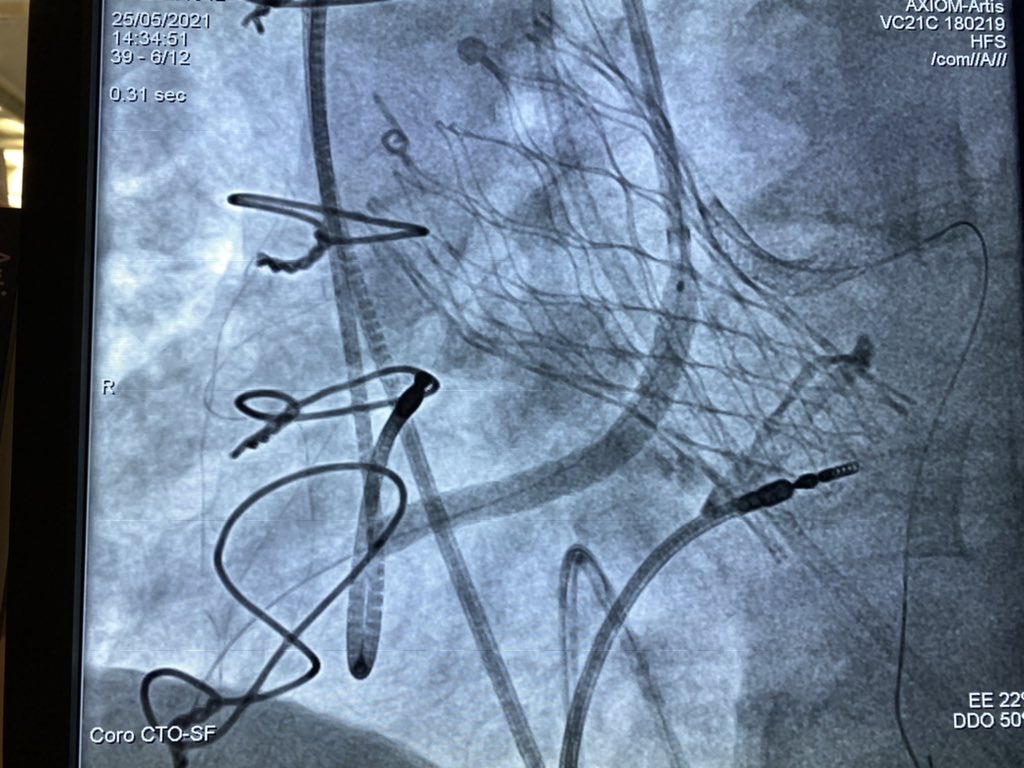

All our possibile tools to treat a severely calcified non crossable and non dilatable lesion: Rotablator, Shockwave and Guide Extension Catheter. Rimini Cath Lab.